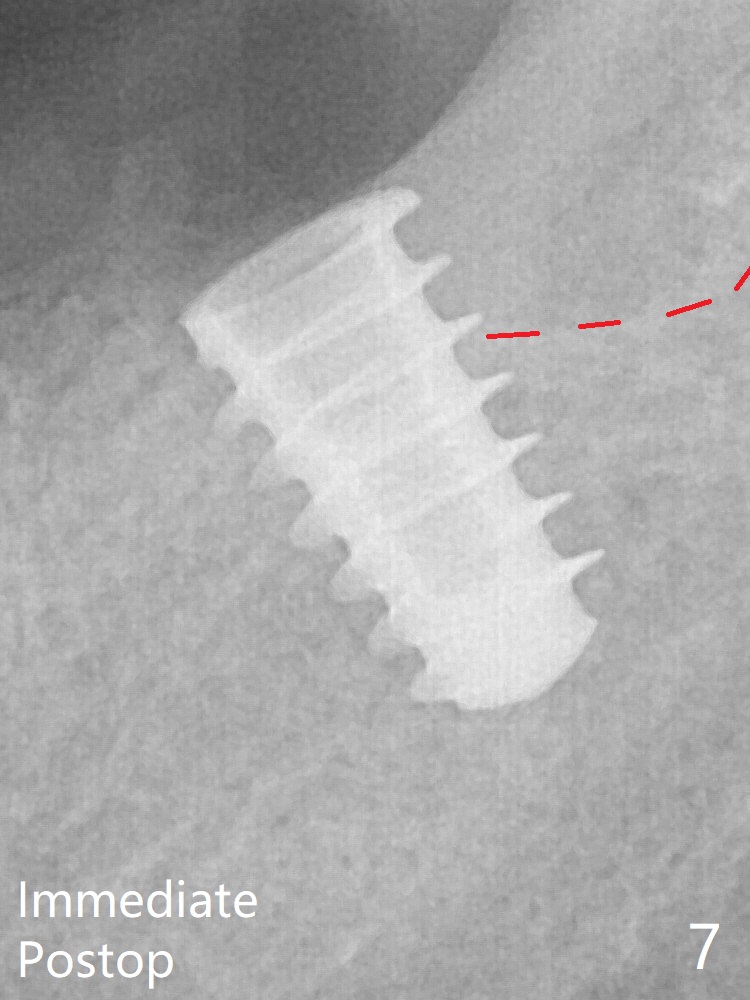

After increase in osteotomy depth for 1-2 mm with MD 4.3 mm, the 5.5x9 mm implant barely obtains stability (~ 10 Ncm, Fig.7). Healing screw is placed. Osteogen plug is inserted in the distal portion of the socket; autogenous bone around the implant and Collagen plug to close the socket opening. Last suture and periodontal dressing are applied.

In fact the distal coronal threads of the implant are exposed due to socket morphology (Fig.2 yellow dashed line, Fig.7 red dashed line). Bone graft should be securely placed immediately distal to the implant to prevent periimplantitis. The implant plateau is covered by the bone 2 years 9 months postop (Fig.8 *).